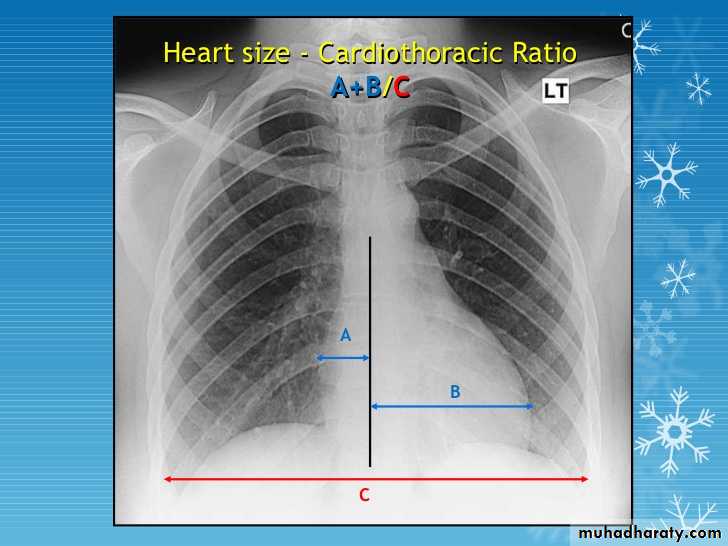

Gastric air bubble on the left & liver on the Rt2/3 of the cardiac shadow lie to the left of midline & one third lie to the Rt